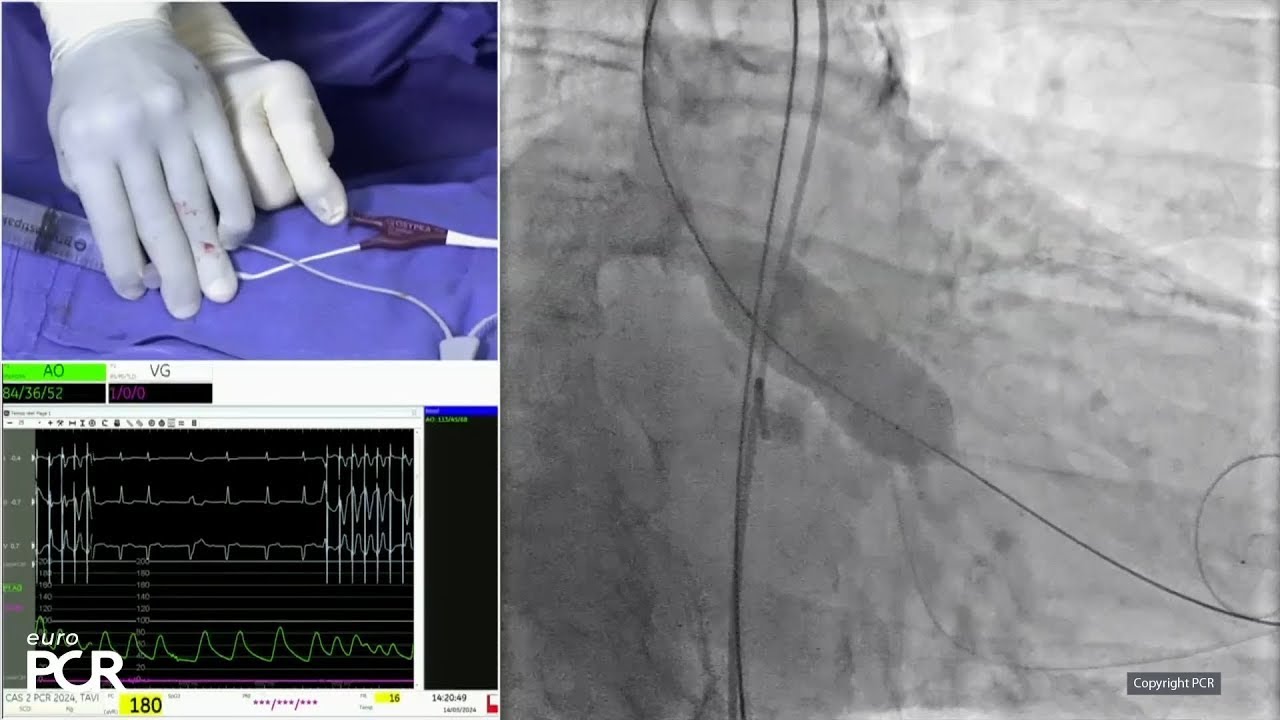

CT scan analysis in live case at EuroPCR 2024